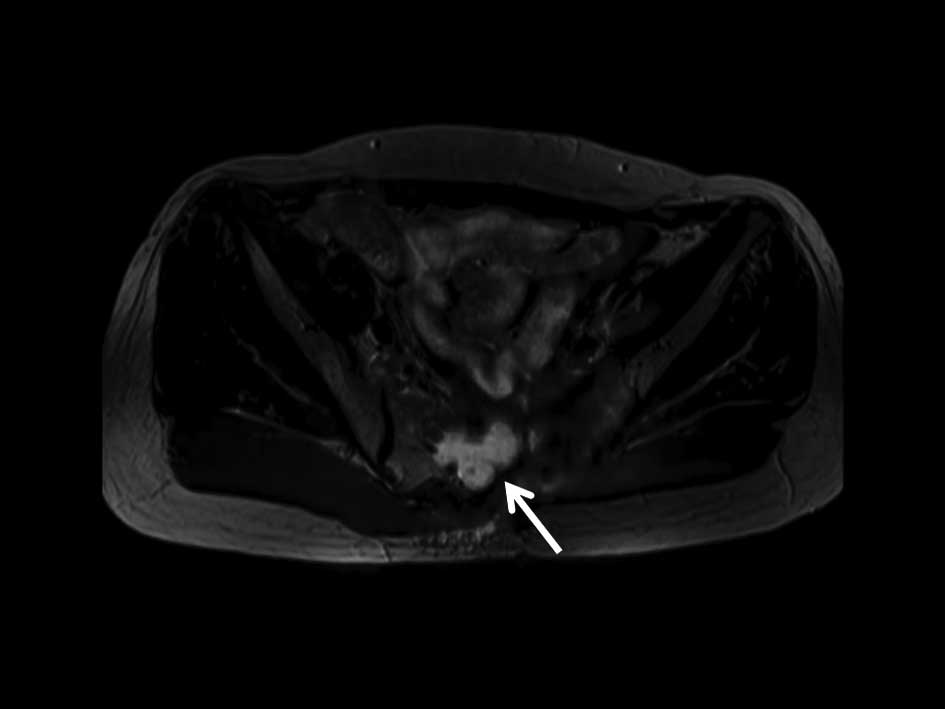

Figure 3

Eight months after surgical removal of the sacral mass, a recurrent tumor is evident on diffusion-weighted magnetic resonance imaging.

PET-CT revealed a localized tumor in the rectum with increased standardized uptake values (SUV) (Fig. 2A). MRI showed a rectal mass adjacent to the prostate capsule without seminal vesicle and/or prostatic involvement (Fig. 2B). DW-MRI revealed a sacral mass in the left half of the bone with diffusion restriction (Fig. 2D). There was no 18F-fluorodeoxyglucose (FDG) uptake in the sacrum on PET-CT images (Fig. 2C). No bone destruction was appreciable on the PET-CT images. A CT-guided bone biopsy was performed and material sampled from the sacrum was found to be positive for mucinous adenocarcinoma. The patient underwent abdominoperineal resection of the rectal tumor that also included removal of the prostate and seminal vesicles with hemisacral excision. The surgery ended with a mesh implantation to restrict bowel motion into the pelvic cavity, to prevent intestinal side effects in case of radiotherapy for locoregional recurrence. Surgical material from the rectum was consistent with mucinous adenocarcinoma and the same as the sacral bone material. The surgical margins were all negative and there was no evidence of contiguous tumor invasion of the sacrum. The patient received five courses of FOLFOX-4 as adjuvant chemotherapy. Eight months subsequent to the pelvic surgery, a follow-up MRI with DW-MRI was performed, which showed a recurrent mass in the sacral bone resection zone (Fig. 3). CT-guided biopsy confirmed the MRI diagnosis. The patient was scheduled for cyber-knife treatment of the sacral mass.